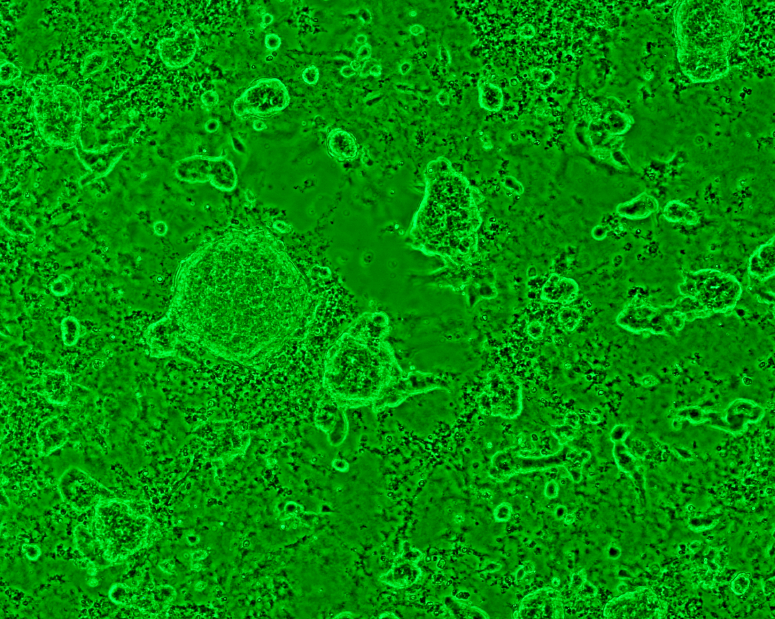

La culture des cellules souches spermatogoniales humaines pour la thérapie cellulaire : où en est-on ?

Source : Hum. Reprod 2014 ; 29(11):2497-511.

Pr Clément Jimenez CHU - Bordeaux

La culture des cellules souches spermatogoniales humaines pour la thérapie cellulaire: où en est-on?